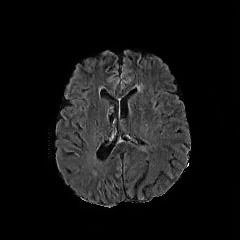

We use two popular medical imaging datasets primarily used for the evaluation of lesion segmentation: the Multimodal Brain Tumor Segmentation Challenge 2018 dataset (BratS18) [21, 2] and the Liver Tumor Segmentation Challenge dataset (LiTS).

BratS18.

The BratS18 dataset provides 210 high grade glioma (HGG) and 75 lower grade glioma (LGG) MRI with binary masks for the tumor (or lack of tumor). Each 3D MRI contains 155 slices of size 240×240240240240\times 240. Not every slice contains a tumor, and therefore healthy MRI are provided by this data as well. We use the FLAIR modality image for all the experiments because the entire tumor is represented well by this modality.However, we also show more experimental results on other modalities, where the ANT-GAN provides impressive visual quality. A more detailed medical description of the data can be found on the challenge website.111https://www.med.upenn.edu/sbia/brats2018.html

LiTS.

We also experiment with the LiTS data containing a total of 131 contrast enhanced abdominal CT volume images of the liver acquired from 7 different clinical institutions. The in-plane resolution ranges from 0.5mm to 1mm and the slice thickness ranges from 0.7mm to 5.0mm. Each slice is 512×512512512512\times 512 in size and we resize them to 256×256256256256\times 256, and as with the BratS18 MRI not every slice contains a lesion and so these slices are considered to be healthy images. A detailed data description can be found on the challenge website. 222https://competitions.codalab.org/competitions/17094

Aside from the difference in imaging tissue and modality of these two data sets, the tumor regions on the CT images are of different shape and size, as can be seen in Figure 4. Also, many CT scans are acquired in a way that introduces greater noise-like artifacts than MRI. For each dataset, 80%percent8080\% of randomly selected data are used for training and the resting 20%percent2020\% for testing.